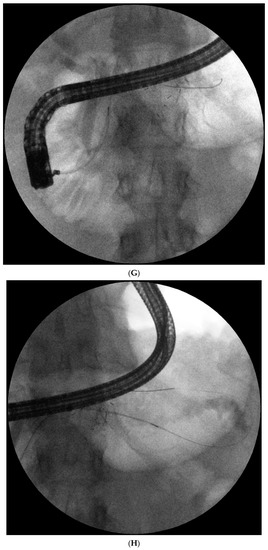

Figure 1. (A–L) Endoscopic treatment of walled-off pancreatic necrosis. In the second week of acute necrotizing pancreatitis, the acute necrotic collection (A) is visible in the abdominal contrast-enhanced computed tomography (CECT), which evolved in the sixth week of the illness duration into the symptomatic walled-off pancreatic necrosis (B). Patient qualified for endoscopic treatment (C–F) transmural drainage using the self-expanding metal stent (C,D) and endoscopic necrosectomy (E,F) was performed. In the second week of endotherapy, the endoscopic retrograde pancreatography (G–J) was performed. During pancreatography, the complete pancreatic duct disruption was stated (G–I) and transpapillary drainage was carried out (J). After achieving the treatment’s success and the complete regression of the necrotic collection, the transpapillary stent was observed in the bottom of the collection via the endoscopic view from the stomach’s side through the transmural stent (K). Control CECT confirmed the total regression of the collection (L).